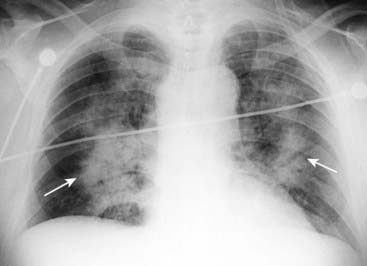

Figure 9-15 Pleural effusions in congestive heart failure.

Bilateral pleural effusions (dotted and solid black arrows) are present in this patient with CHF. Effusions in CHF are most often bilateral but may be asymmetrical, the right side invariably being slightly larger. While a unilateral, left pleural effusion may occur with CHF, a large left effusion should draw suspicion to another possible cause, such as metastatic disease.